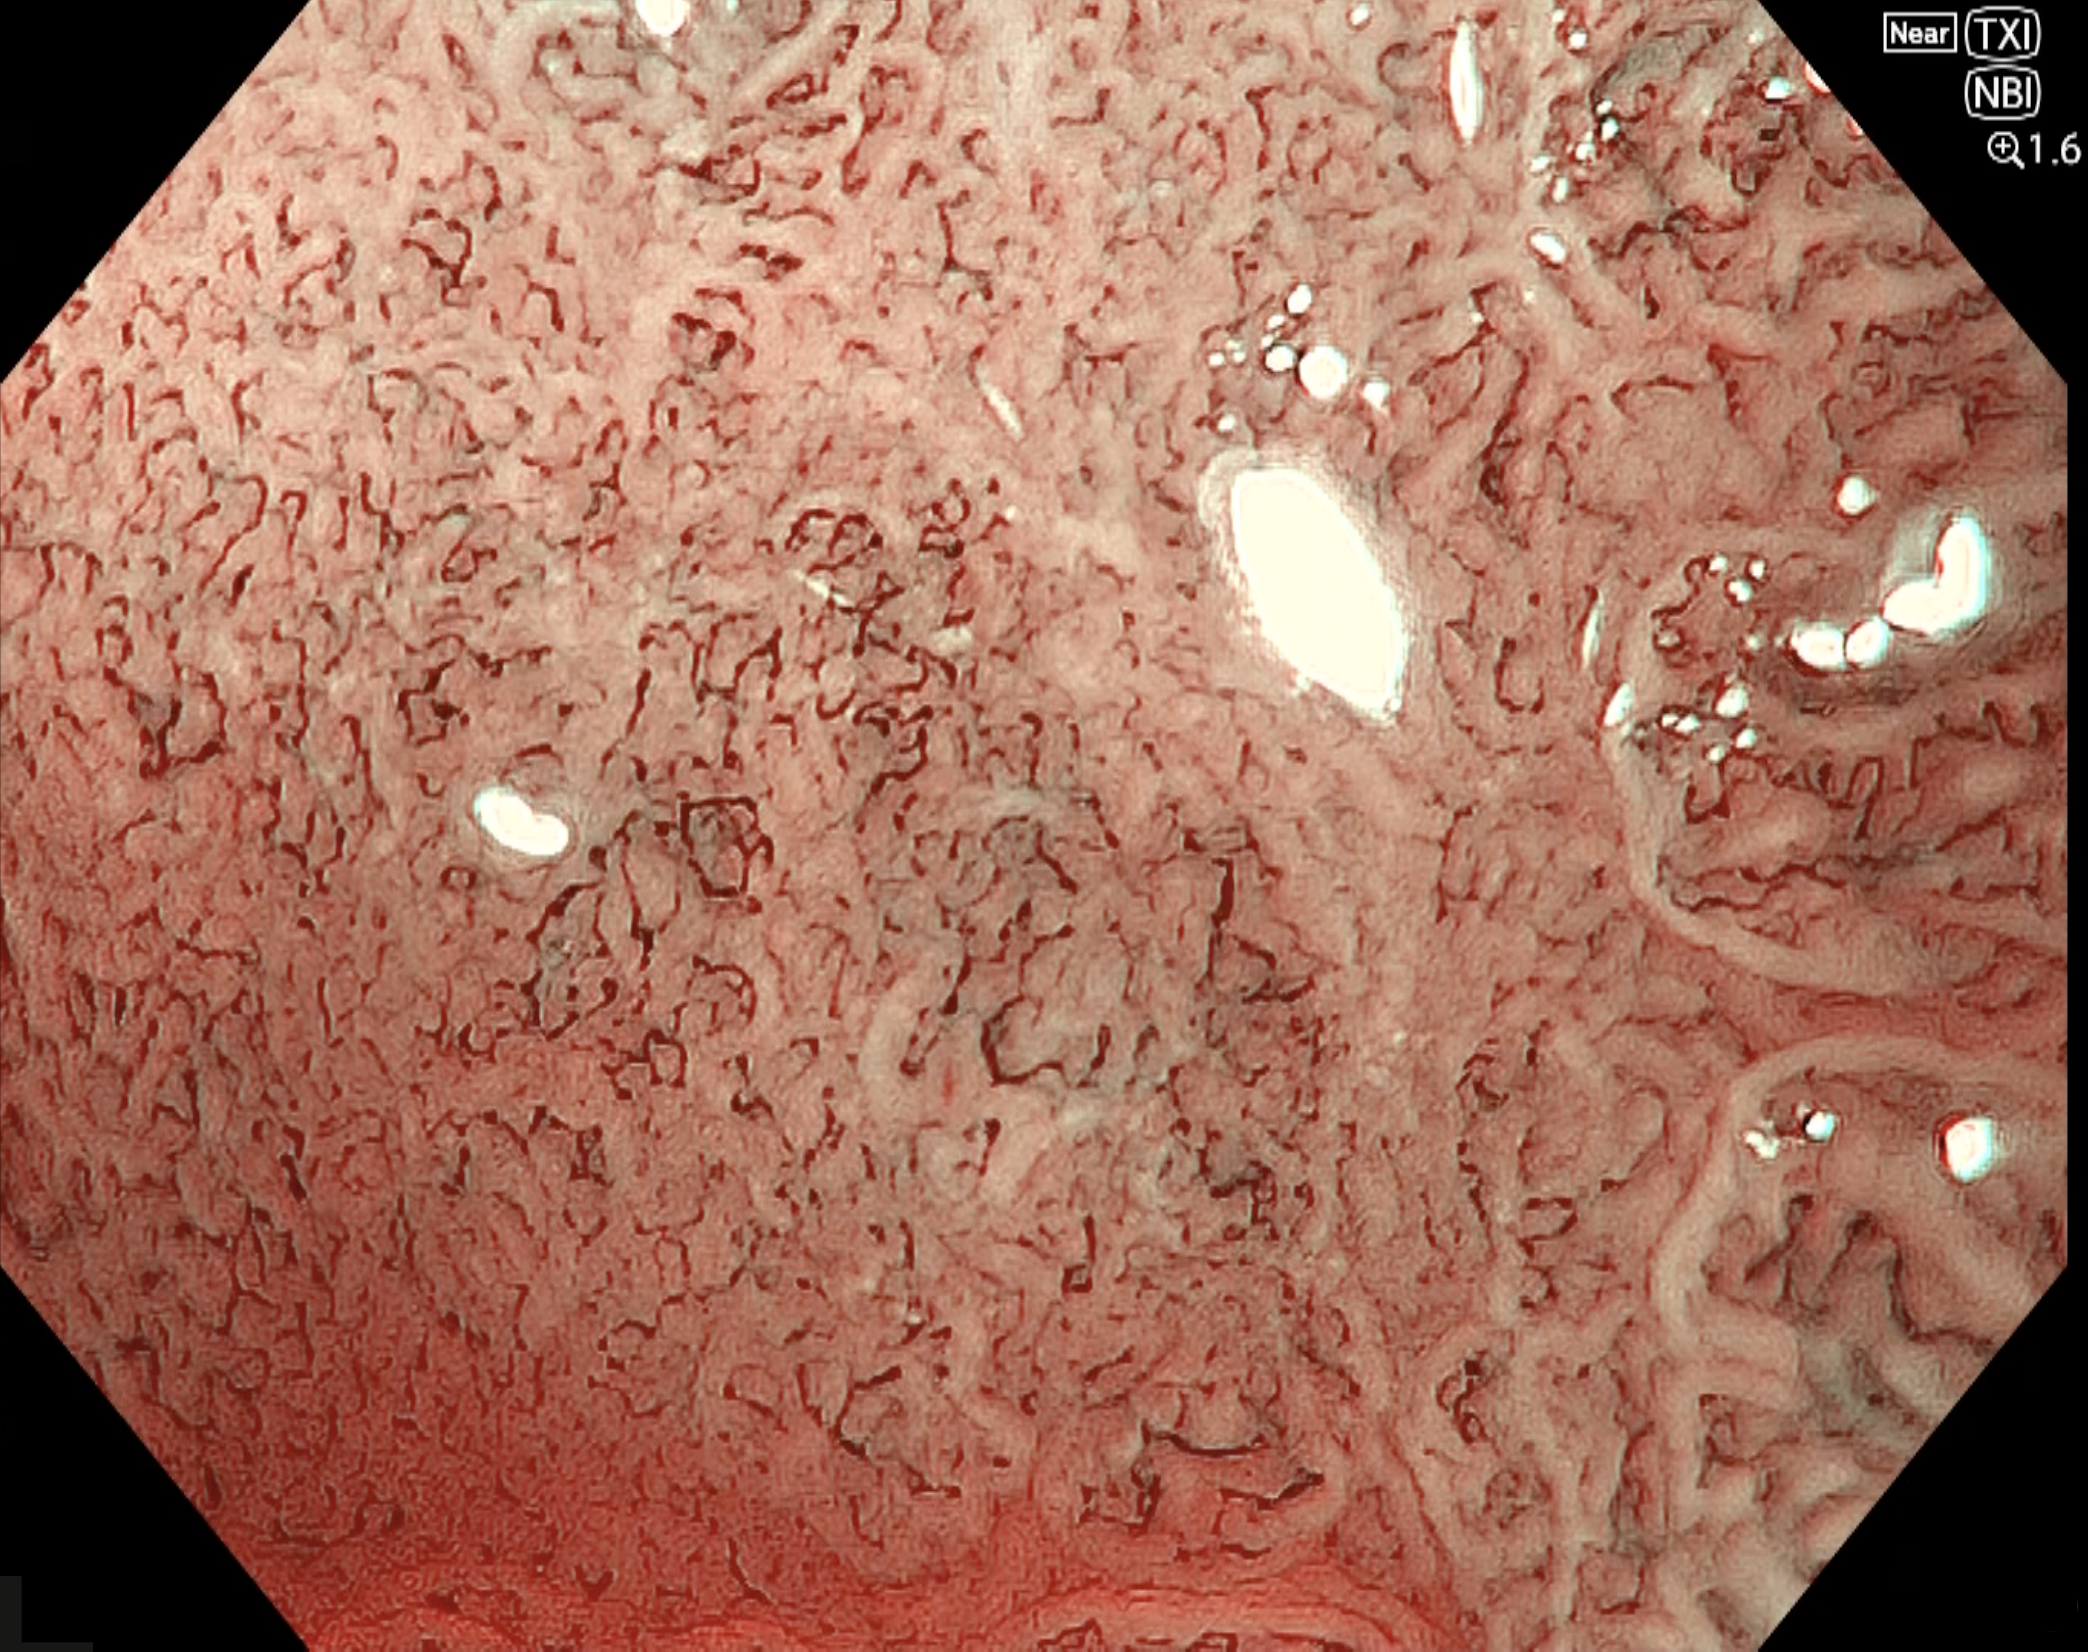

• NBI観察(電子拡大)

強調設定:B8

図6

near focusモードに電子拡大1.6倍を併用することで、腫瘍肛門側における表面微細構造および微小血管構築像の詳細観察が可能となっている。